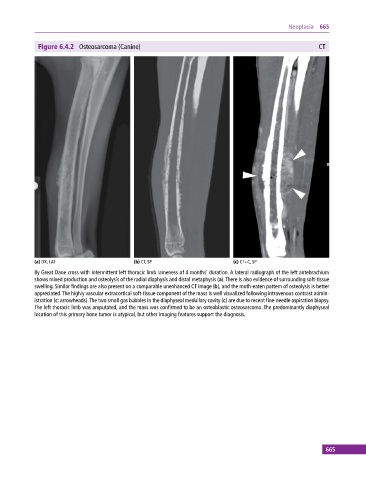

Figure 6.4.2 Osteosarcoma (Canine) CT

(a) DX, LAT (b) CT, SP (c) CT+C, SP

8y Great Dane cross with intermittent left thoracic limb lameness of 4 months’ duration. A lateral radiograph of the left antebrachium

shows mixed production and osteolysis of the radial diaphysis and distal metaphysis (a). There is also evidence of surrounding soft‐tissue

swelling. Similar findings are also present on a comparable unenhanced CT image (b), and the moth‐eaten pattern of osteolysis is better

appreciated. The highly vascular extracortical soft‐tissue component of the mass is well visualized following intravenous contrast admin-

istration (c: arrowheads). The two small gas bubbles in the diaphyseal medullary cavity (c) are due to recent fine‐needle aspiration biopsy.

The left thoracic limb was amputated, and the mass was confirmed to be an osteoblastic osteosarcoma. The predominantly diaphyseal

location of this primary bone tumor is atypical, but other imaging features support the diagnosis.